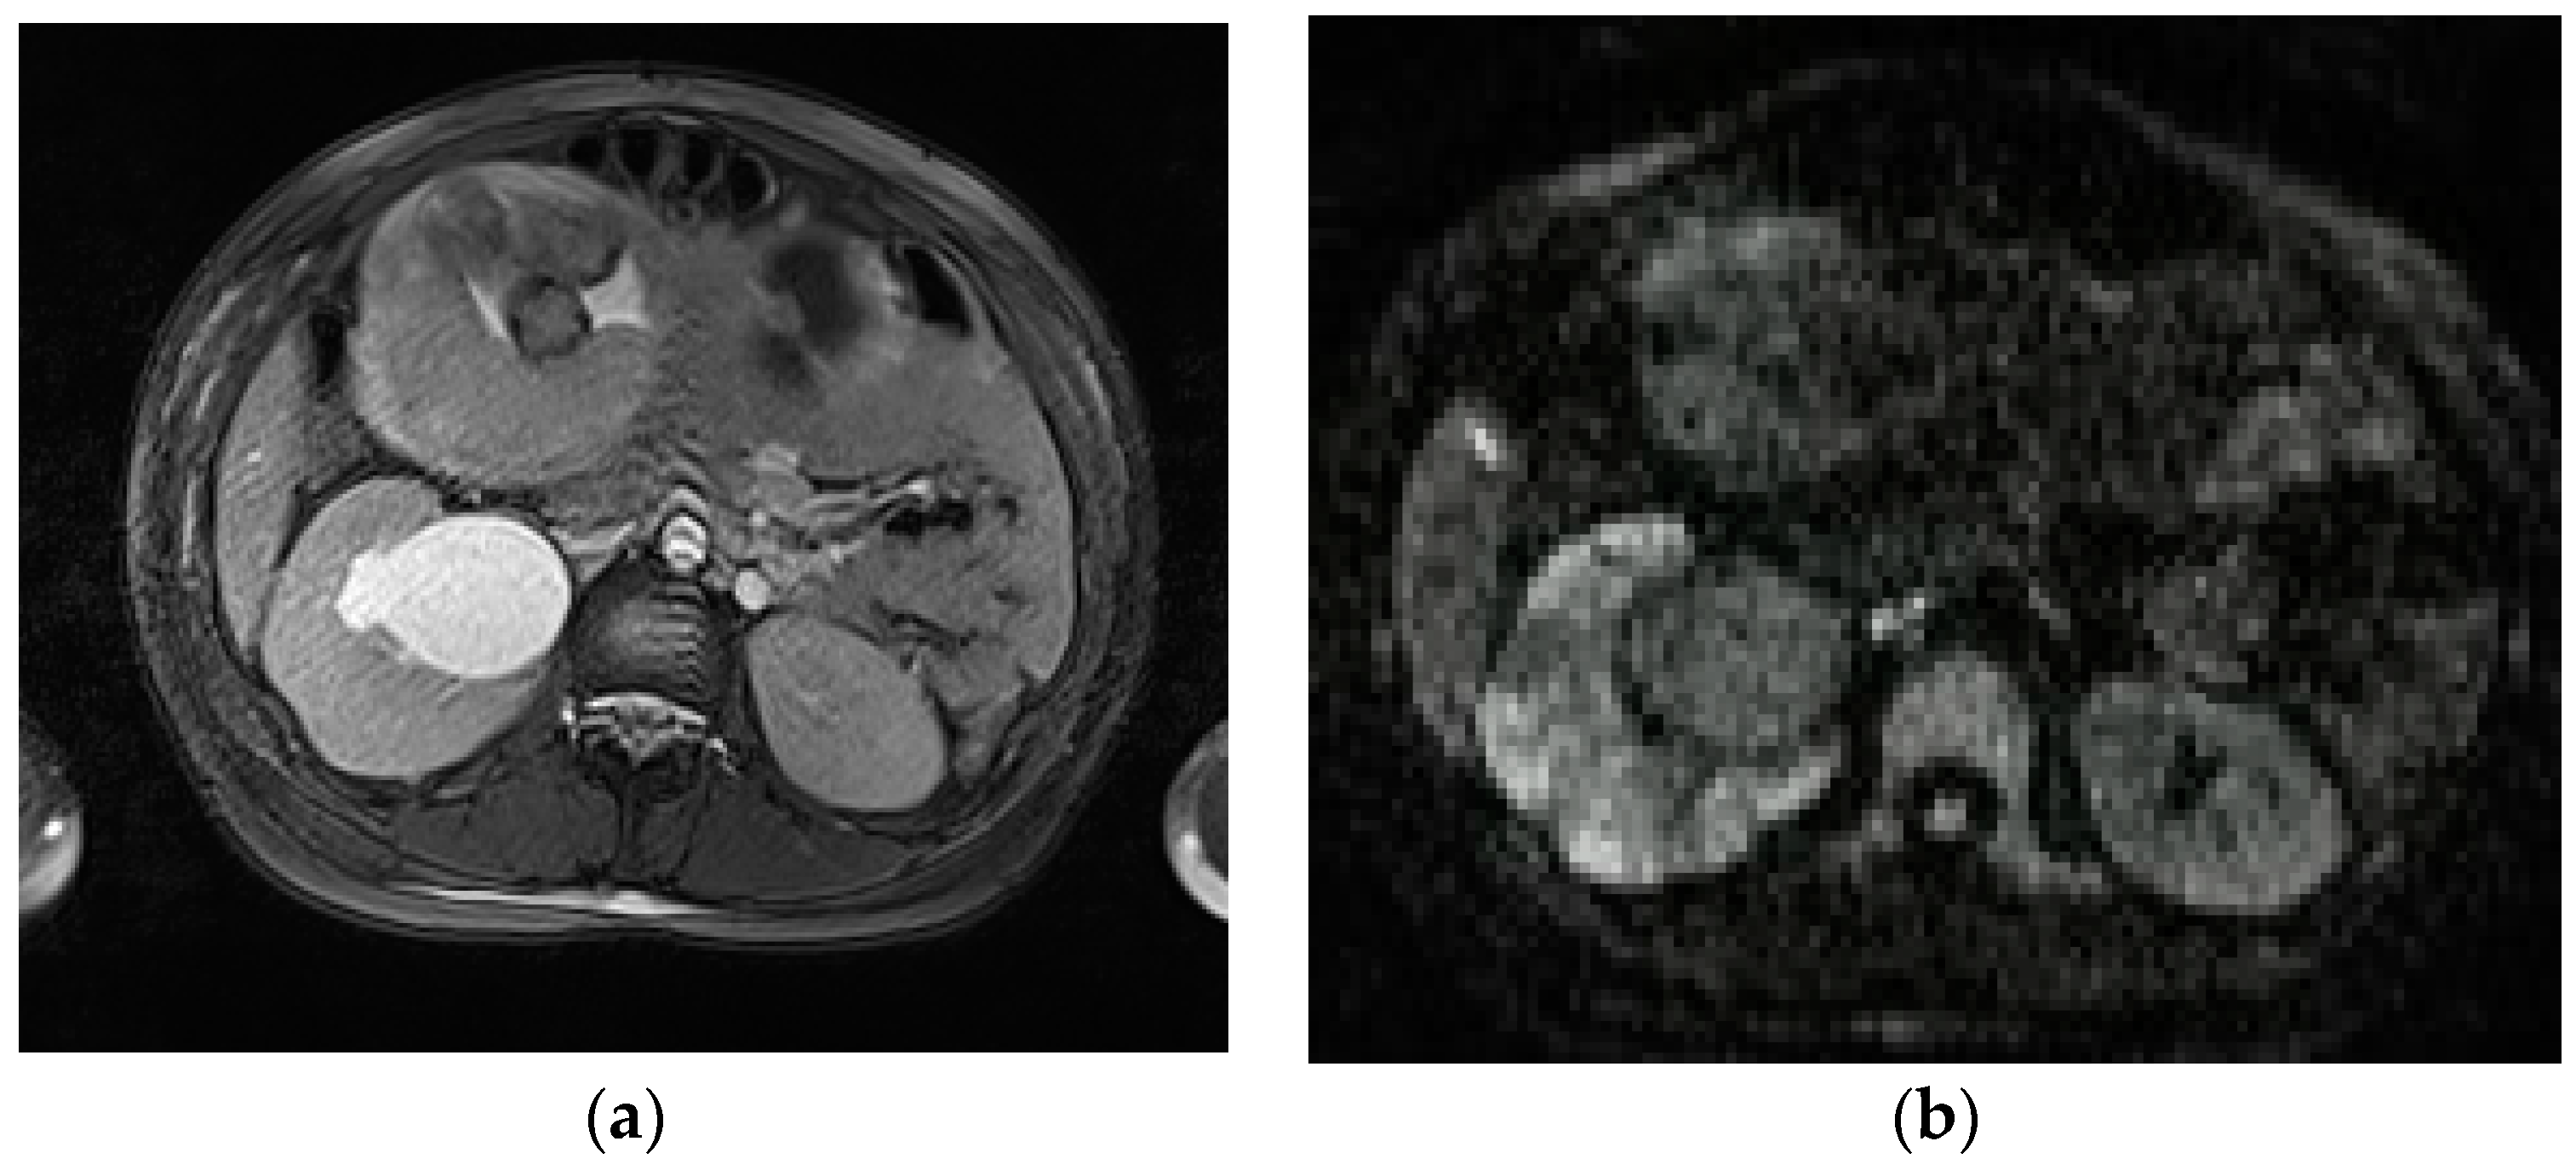

The impaired egress of urine (urinary stasis), due to stones, increases the risk of complications, such as acute pyelonephritis, reported in 1% of pregnancies [80]; in these cases, MRI could be a useful adjunct to clinical diagnosis. The DWI sequence in particular has been found to have increased sensitivity when compared to non-contrast CT (95% and 67%, respectively). The kidney appears enlarged and edematous with areas of lower signal intensity on T2-weighted images and restricted diffusion on DWI (Figure 7).

Figure 7.

Acute pyelonefritis in a 28-year-old woman at 23 weeks of gestation presenting with right-sided abdominal pain and fever. Axial T2WI fat-sat image (a) shows an enlarged right kidney with a dilated pelvis. Axial DWI b-800 (b) clearly depicts wedge-shaped areas of high signal intensity in the right kidney, consistent with the foci of nephritis.

In patients who develop renal abscesses, T2-weighted and DW images respectively show a focal, more hyperintense signal and restricted diffusion, compared to the rest of the parenchyma involved in nephritis [3,54] (Figure 8).

Figure 8.

A 21-year-old woman at 20 weeks of gestation was admitted to the hospital with a diagnosis of pyelonephritis and a temperature of 39.4 °C. Coronal T2-weighted HASTE (a) and axial T2-weighted fat-sat images (b) show a large right-sided and thick-walled fluid collection (arrows), consistent with renal abscess, displacing the kidney.